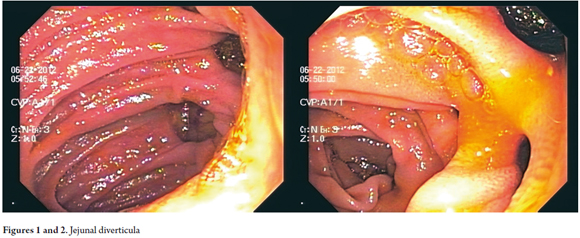

The patient was an 80-year old woman with a history of hypertension and irritable bowel syndrome who was admitted to the emergency department of the Reina Sofia Clinic in Bogotá, Colombia. The patient presented hematochezia indicating lower gastrointestinal bleeding. The patient's evaluation showed hypotension, tachycardia, hemoglobin decreased to 8 and hematocrit decreased to 28.5. The patient was stabilized hemodynamically, given a transfusion and prepared for colonoscopy and endoscopy. The endoscopy report was "antral atrophic gastritis?", and the colonoscopy report showed severe colon diverticulum disease. The colonoscopy also showed the presence of abundant fresh red blood residue although it was unable to identify a site of bleeding up to the cecum. During the second day of hospitalization the patient experienced rebleeding with hemoglobin decreased to 6, hematocrit decreased to 20, rectal bleeding and hemodynamic instability. This required another transfusion of 4 units of red blood cells. Another endoscopy and another colonoscopy were performed but could not document the bleeding area despite thorough cleaning. Nevertheless, hematic material was found in the terminal ileum. The patient was stabilized but presented another episode of rebleeding on the third day which required transfer to the ICU and multiple transfusions. Given these findings and the patient's critical condition, enteroscopy was performed (with an Olympus balloon enteroscope). This revealed the presence of numerous wide-mouthed diverticula in the proximal and medial jejunum (figures 1 and 2). One of these showed recent bleeding. The tissue was hardened and marked with an Indian ink tattoo (figures 3 and 4). The patient's case was presented to the board which decided on performance of a surgical procedure. The tattooed area, a 15cm jejunal segment, was excised through laparoscopic intestinal resection. Following the intervention the patient's recovery was good, and she was discharged from the clinic on the eight day. At present, the patient's one year follow-up and monitoring have shown no recurrences of bleeding.